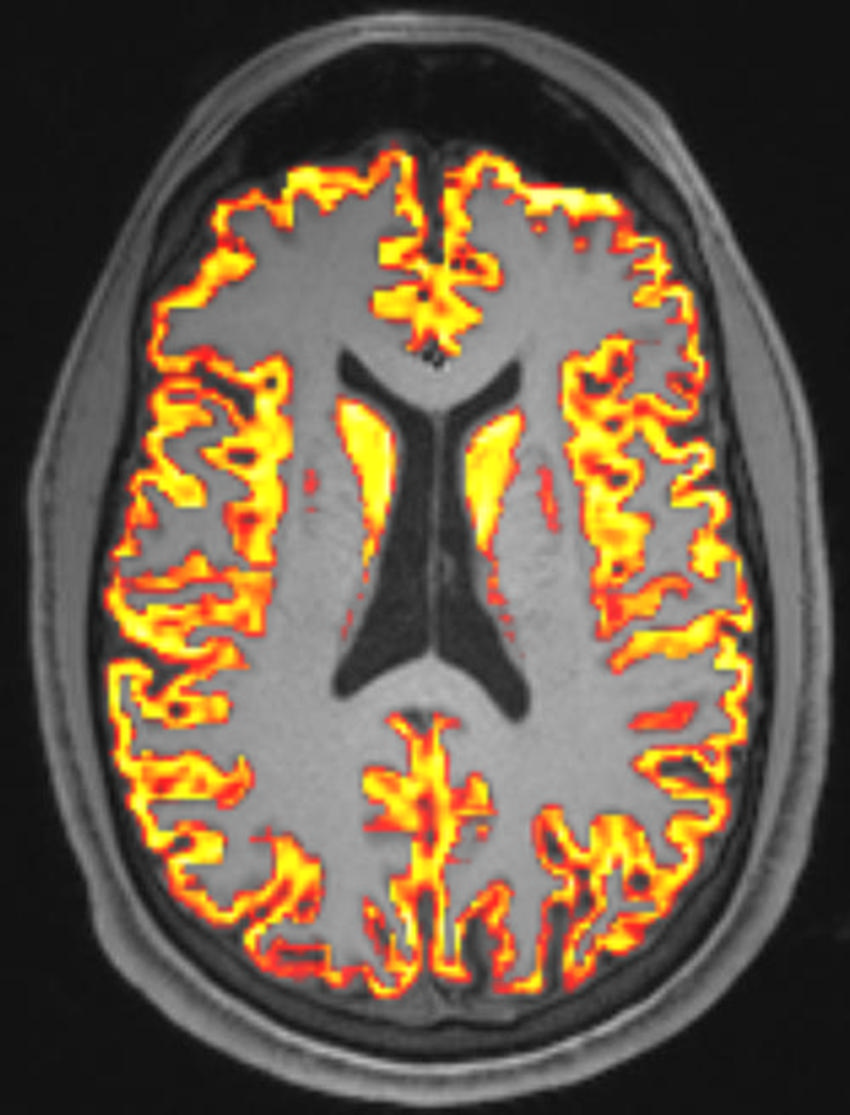

DMI looks at the movement of water molecules in tissues. By studying how water molecules move in different directions and at various speeds, DMI can provide detailed information on the microstructure of the brain. It can detect even very small changes in the brain, not detectable with conventional MRI.

The three groups were compared to reveal group differences in the brain's microstructure. DMI parameters were read for the gray matter in the brain. Additionally, whole brain analyses were employed to reveal the spatial distribution of alterations and associations with clinical data, including long-COVID symptoms like fatigue, cognitive impairment or impaired sense of smell.

The results showed no brain volume loss or any other lesions that might explain the symptoms of long COVID. However, COVID-19 infection induced a specific pattern of microstructural changes in various brain regions, and this pattern differed between those who had long COVID and those who did not.

Figure 1. Axial T1-weighted MRI with a microstructural parameter map obtained superimposed over the gray matter.